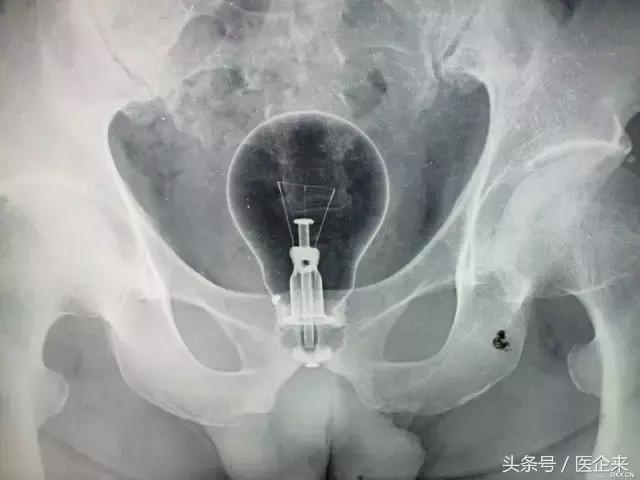

11. 电灯泡,经肛进入,保持完整(这是什么骚操作?很是佩服了!)